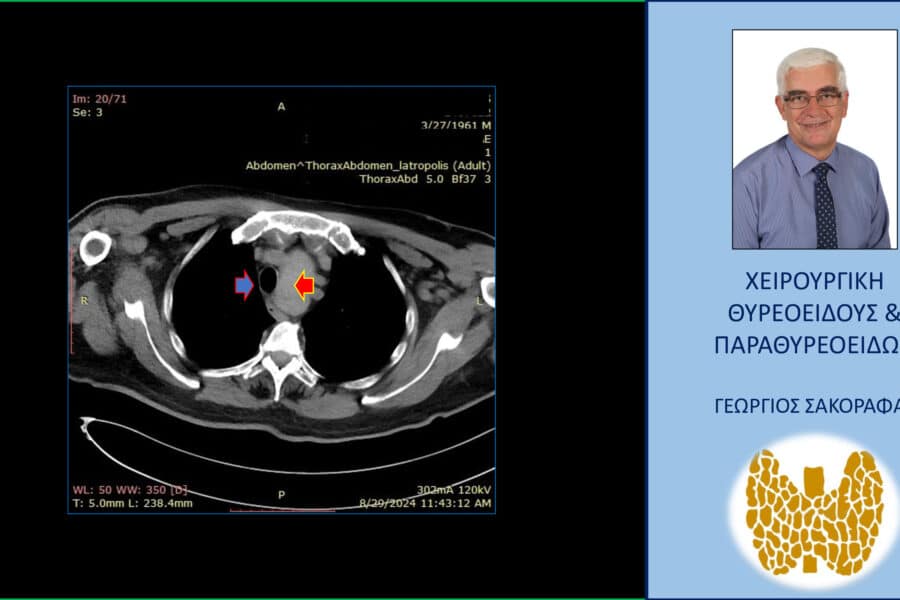

Όζοι θυρεοειδούς και συμπληρωματική θυρεοειδεκτομή (completion thyroidectomy) – με αφορμή ασθενή μας Παρουσίαση ασθενούς Αιτία…